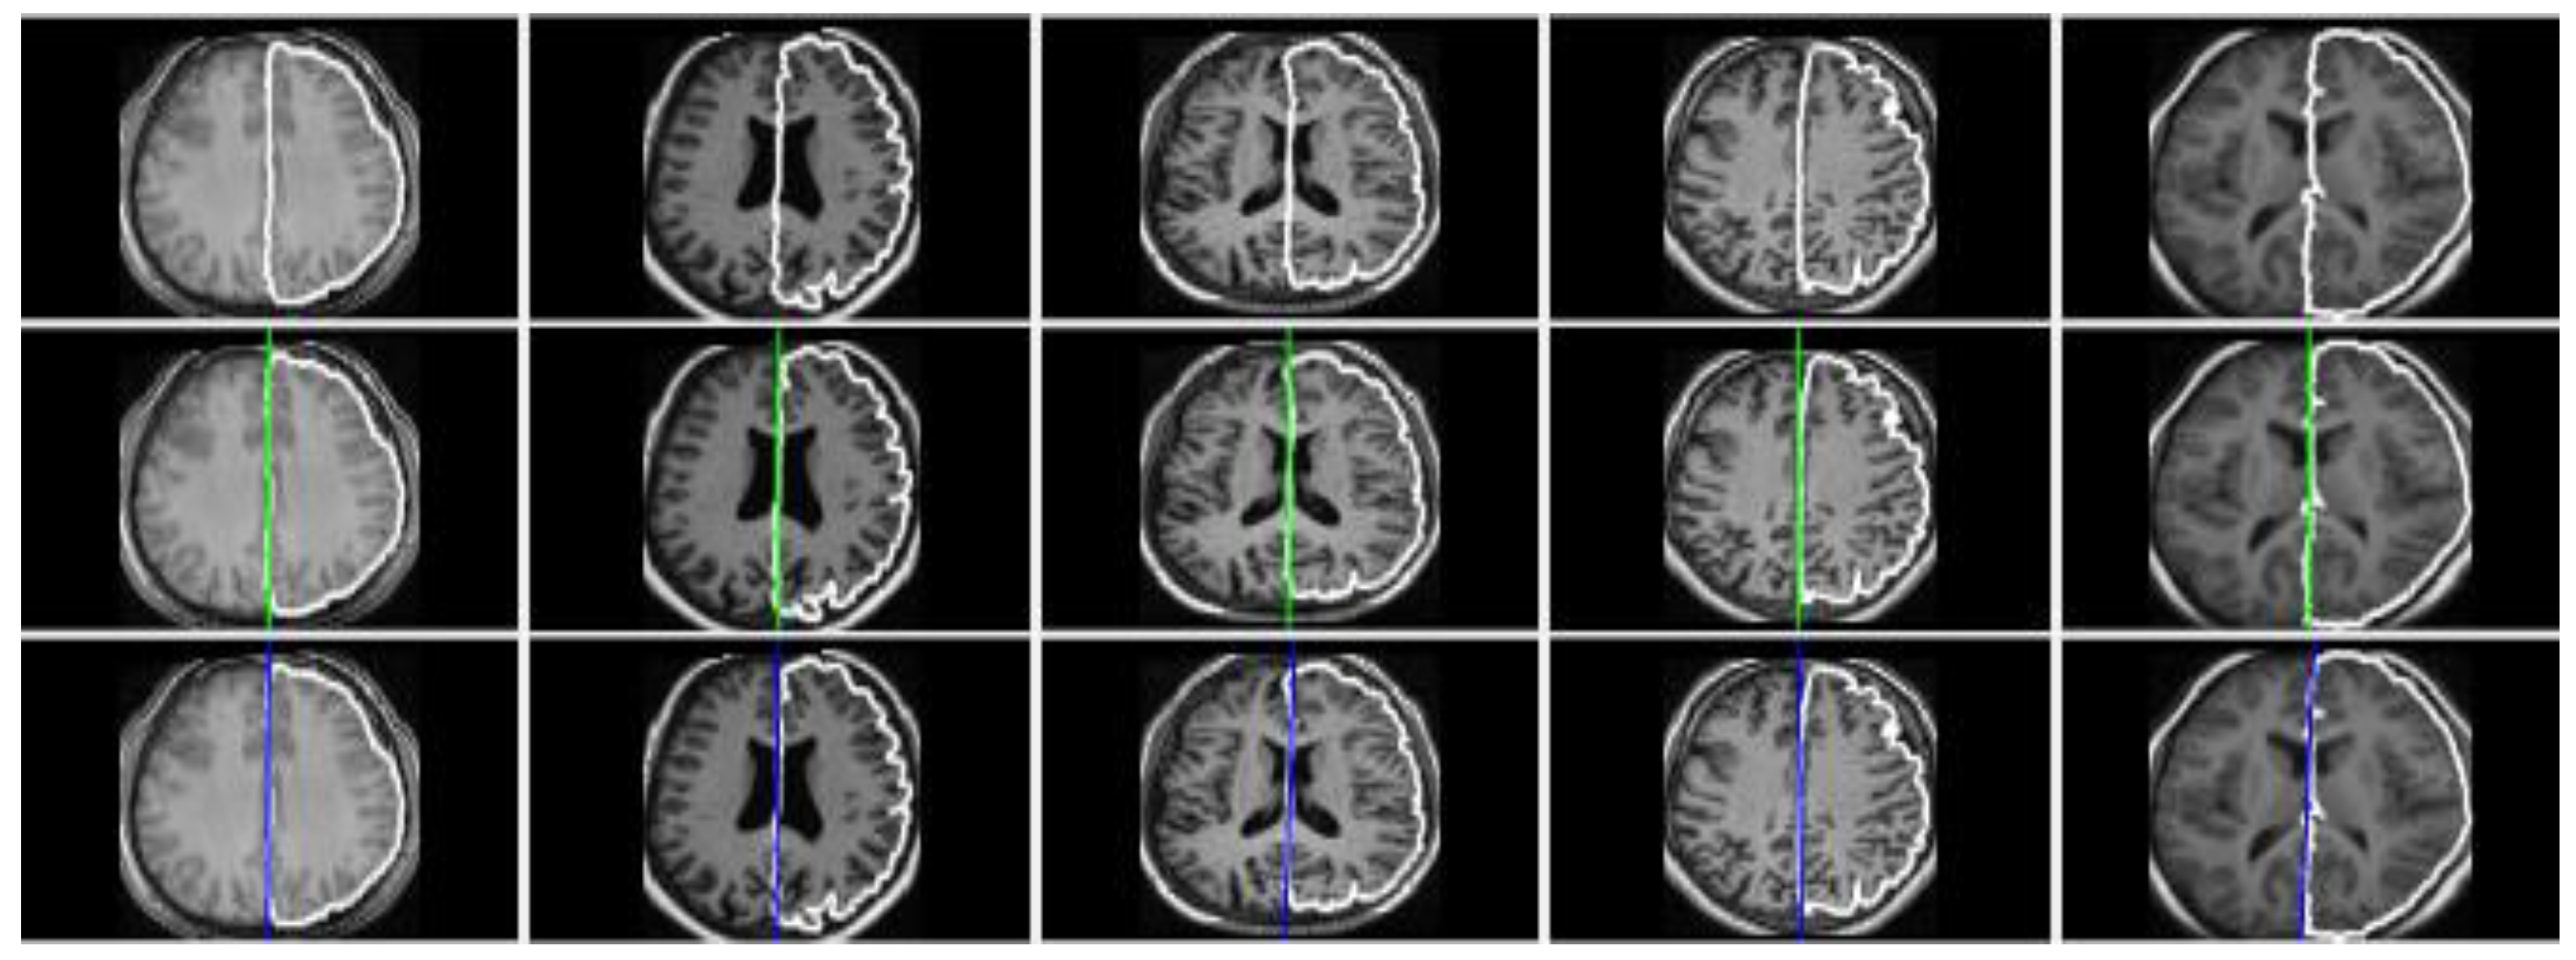

3. Results and Discussion

3.1. Evaluation on Real Datasets